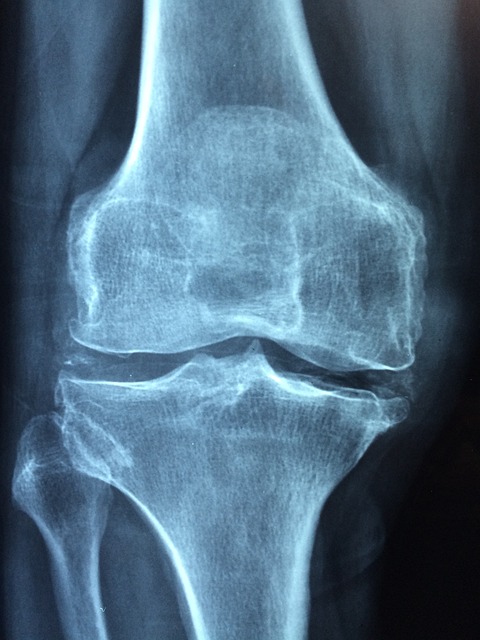

전문 치료는 언제 필요할까?

관절이 부어오르거나 극심한 통증이 지속되면 전문의를 찾아 정확한 진단을 받는 것이 중요합니다.

조기 치료는 퇴행성 관절염 등 심각한 질환으로 진행되는 것을 막아줍니다.